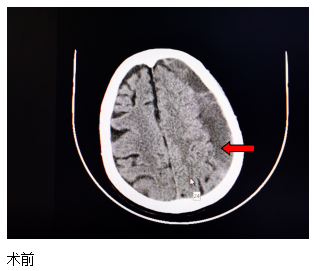

近日,一位84歲高齡患者來江寧中院就診,表現(xiàn)為:右側(cè)肢體的力量下降、不能獨(dú)立站立、言語不利、吐字不清。經(jīng)頭部CT檢查發(fā)現(xiàn),患者左側(cè)大面積慢性硬膜下血腫,嚴(yán)重壓迫腦組織。

患者收入院后,完善各項(xiàng)檢查,無明顯手術(shù)禁忌,中醫(yī)院神經(jīng)外科團(tuán)隊(duì)經(jīng)過精心周全的準(zhǔn)備,為其實(shí)施了腦膜中動(dòng)脈栓塞結(jié)合硬通道血腫穿刺引流的復(fù)合手術(shù)。術(shù)后第二天,患者肢體無力的癥狀得到了明顯改善,語言表達(dá)也恢復(fù)如初?;颊呒凹覍賹?duì)此治療效果非常滿意。